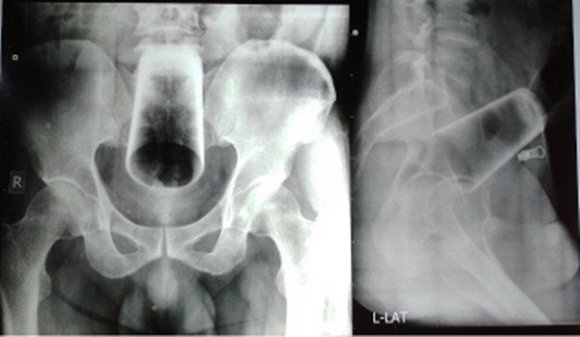

항문으로 유리컵을 삽인한 남성의 엑스레이 사진. (네팔 의학협회 저널)

남성은 변비로 인한 극심한 고통을 호소했지만 의료진은 남성에게서 별다른 외상을 찾을 수 없었다. 복부가 부어있는 상태도 아니었으며 항문에도 상처나 출혈이 없어 의료진은 엑스레이 촬영을 실시했다. 그 결과 남성의 복부 한가운데서 12㎝의 유리컵이 발견됐다.

의료진은 항문을 통해 유리컵을 빼내려고 시도했으나 유리컵이 뒤집혀 있는 데다 깨질 위험이 높아 결장절개술로 유리컵을 제거했다.